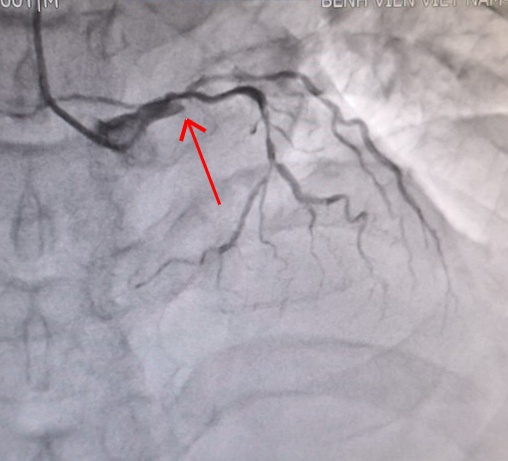

Mạch vành của người bệnh trước và sau khi can thiệp. |

Các bác sĩ đã chụp mạch vành xâm lấn qua da để đánh giá mức độ tổn thương và kịp thời can thiệp cho người bệnh. Kết quả cho thấy người bệnh có tổn thương nặng ba thân động mạch vành, trong đó có nhánh động mạch vành trái bị tắc cụt hoàn toàn…

Theo các bác sĩ khoa Nội tim mạch, đây là trường hợp nhồi máu cơ tim rất phức tạp, hẹp cả 3 thân động mạch vành chính gây thiếu máu nuôi dưỡng cho tim, nguy cơ tử vong rất cao.

Các bác sĩ đã nhanh chóng đặt stent động mạch vành trái cho bệnh nhân. Sau thời gian điều trị, người bệnh đã hồi phục và được ra viện trong niềm vui, phấn khởi của gia đình.